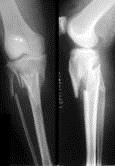

问题 病历摘要: 患者×××,男性,65岁,因车祸致伤左小腿后肿胀、活动受限、疼痛2小时。查体:左小腿上端肿胀,触痛(+),触及在骨擦音,左足伸足母、伸趾功能正常,足背动脉搏动正常。 关于胫骨平台骨折的分型以下叙述哪些是正确的?

选项 A、Ⅳ型:"T"型与"Y"型骨折或两髁的粉碎性骨折,有时合并髁间隆凸骨折,外侧平台往往损伤很严重 B、Ⅱ型:单纯压缩骨折,发生过度外翻,外侧胫骨平台被股骨外髁压塌,平台本身增宽 C、Ⅲ型:Ⅰ型与Ⅱ型合并与关节面压缩及外侧皮质骨折,在前后位X线片上胫骨平台往往增宽,在侧位相上,关节面前部或后部完全压缩 D、Ⅰ型:单纯楔型骨折,比较少见,最常见是外侧或后侧,如果出现在内侧则有相应内翻畸形,骨折面可以在冠状面或矢状面